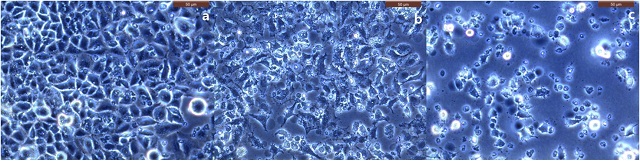

▲ (A)배양된 폐암세포, Cu-67 투여 전 광학영상, (B)사멸된 폐암세포 (20%), Cu-67 투여 후 8시간 경과, (C)사멸된 폐암세포 (80%) Cu-67 투여 후 24시간 경과 (사진 : 한국원자력연구원)